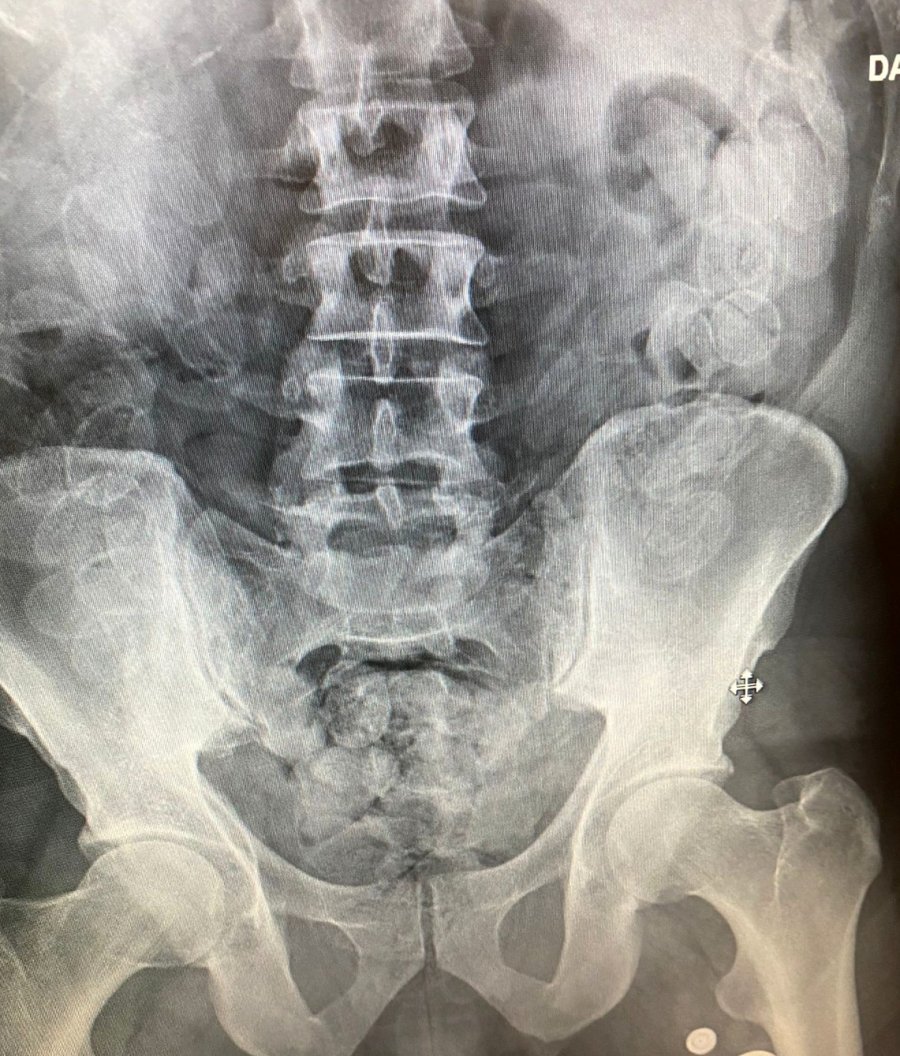

Antalya'da Narkotik Suçlarla Mücadele Şube Müdürlüğü Hudut Kapıları Büro Amirliğince Antalya Havalimanı'na gelen Fas uyruklu şahsın şüpheli tavırlar sergilemesi üzerine yaptırılan iç beden muayenesinde 100 adet kapsül halinde daralı bin 100 gram macun esrar maddesi yakalandı.

Antalya Havalimanı'na gelen Fas uyruklu H.L.'nin şüpheli tavırlar sergilemesi üzerine Narkotik Suçlarla Mücadele Şube Müdürlüğü Hudut Kapıları Büro Amirliği ekiplerince yaptırılan iç beden muayenesinde 100 adet kapsül halinde daralı bin 100 gram macun esrar maddesi yakalandı. Gözaltına alınan şüpheli H.L. hakkında "Uyuşturucu veya Uyarıcı Madde Ticareti Yapma veya Sağlama" suçlarından işlem yapıldı.